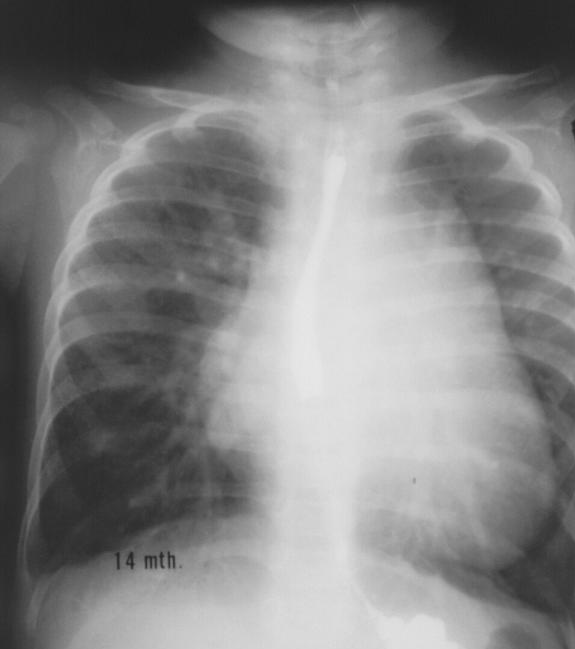

慢性肺源性心脏病

"雪人征":心上型肺静脉异位引流.